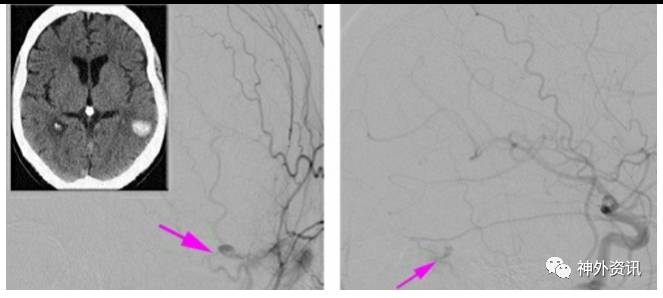

图4. 一例自发性右侧矢状窦旁dAVF,主要由硬脑膜中动脉分支供血(上图,侧位和前后位颈外动脉造影)。夹闭汇入上矢状窦的主要动脉化引流静脉(左下图)。接着,相关的皮层曲张静脉和引流静脉都转为蓝色(右下图,箭头)。